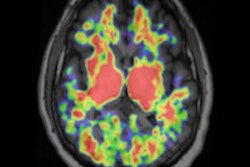

| Lef to right: Images of PiB and myocardial blood flow (MBF) in patients with high, intermediate, and partially increased PiB retention and a healthy control. The liver is clearly visible in PiB images of one patient (second from left) and in the healthy control, and is just outside PET field-of-view in two other patients. Liver uptake is due to biliary excretion of PiB and is likely not related to amyloid binding. Images courtesy of the Journal of Nuclear Medicine. |

On the other hand, PiB-PET detected signs of pathology. Researchers discovered an "obvious uptake" of PiB in the left ventricle wall of all patients with cardiac amyloidosis, but no uptake of PiB in the healthy volunteers. In half of the patients, PiB was also detected in the right ventricle wall, while nine patients had signs of reversible uptake, with a maximum concentration at 10 to 15 minutes after PiB injection.

Myocardial blood flow was significantly lower in patients with cardiac amyloidosis, but the researchers found no significant correlation between myocardial blood flow and PiB uptake.